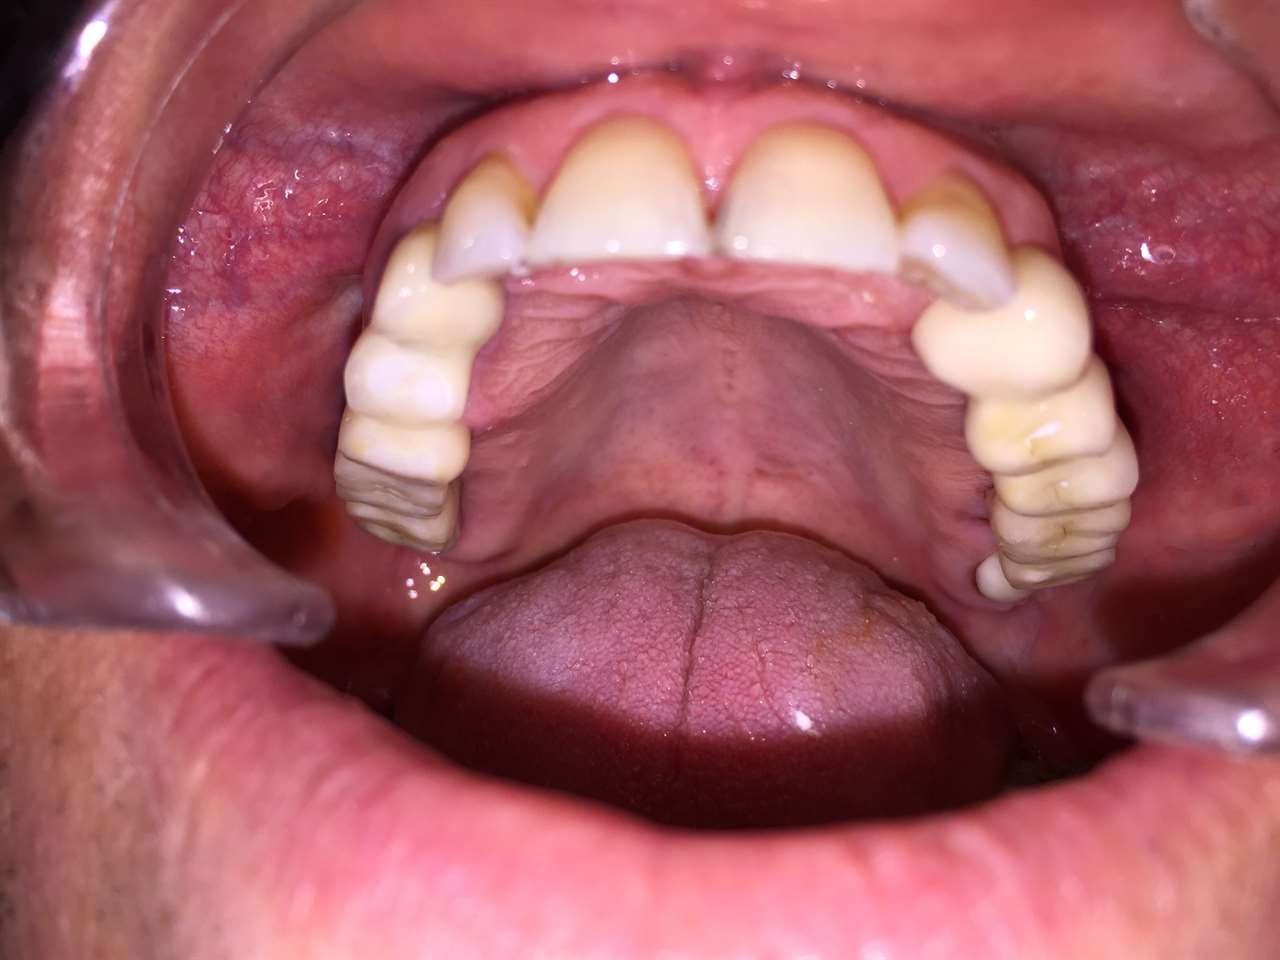

Teljes szájüregi rehabilitáció két lépésben

Ismét egy teljes szájüregi rehabilitáció két lépésben. Először az alsó fogak lettek kihúzva és azonnal implantálva, híddal ellátva, majd később a felső. IHDE svájci azonnal terhelhető implantátumok és cirkónium hidak. Dr. Kelemen Péter és a Symbion Fogtechnika közös munkája.